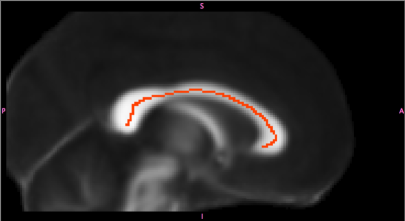

In our data set, FA was measured at 107 voxels (volume units) in 146 individuals age 7–48. These mm voxels, based on registration to the FMRIB58_FA standard space image (http://fsl.fmrib.ox.ac.uk/fsl/fslwiki/FMRIB58_FA), trace a path along a midsagittal cross-section of the corpus callosum (see Figure 1). We take to represent arc length along this path, which ranges from mm (the leftmost point in the figure, toward the back of the brain) to mm. At right in Figure 1, a rainbow plot (Hyndman and Shang, 2010), with FA curves color-coded by age, is used to visualize the relationship between age and the functional response. This relationship appears quite noisy and possibly non-monotonic (and hence nonlinear) in some locations.